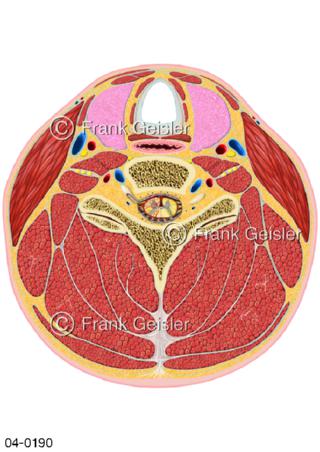

Bildergalerie Topografie Organe

Bilder zur topografischen Anatomie, die Lage der Organe und die Strukturen nach ihren räumlichen Lagebeziehungen zueinander, Übersicht der inneren Organe im Kopf und im Rumpf, Topografie der Organe im Brustraum (Thorax) und im Bauchraum (Abdomen)